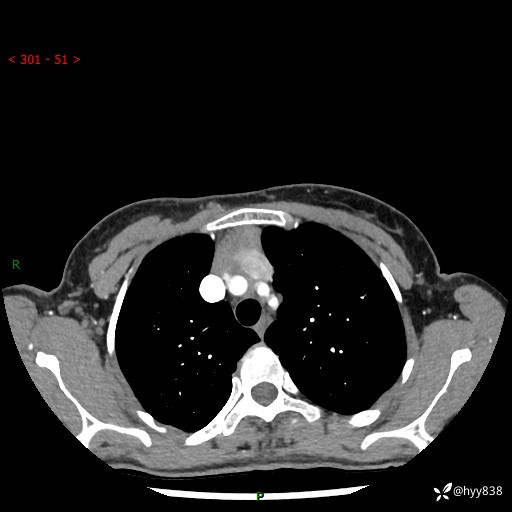

增强动脉期+静脉期